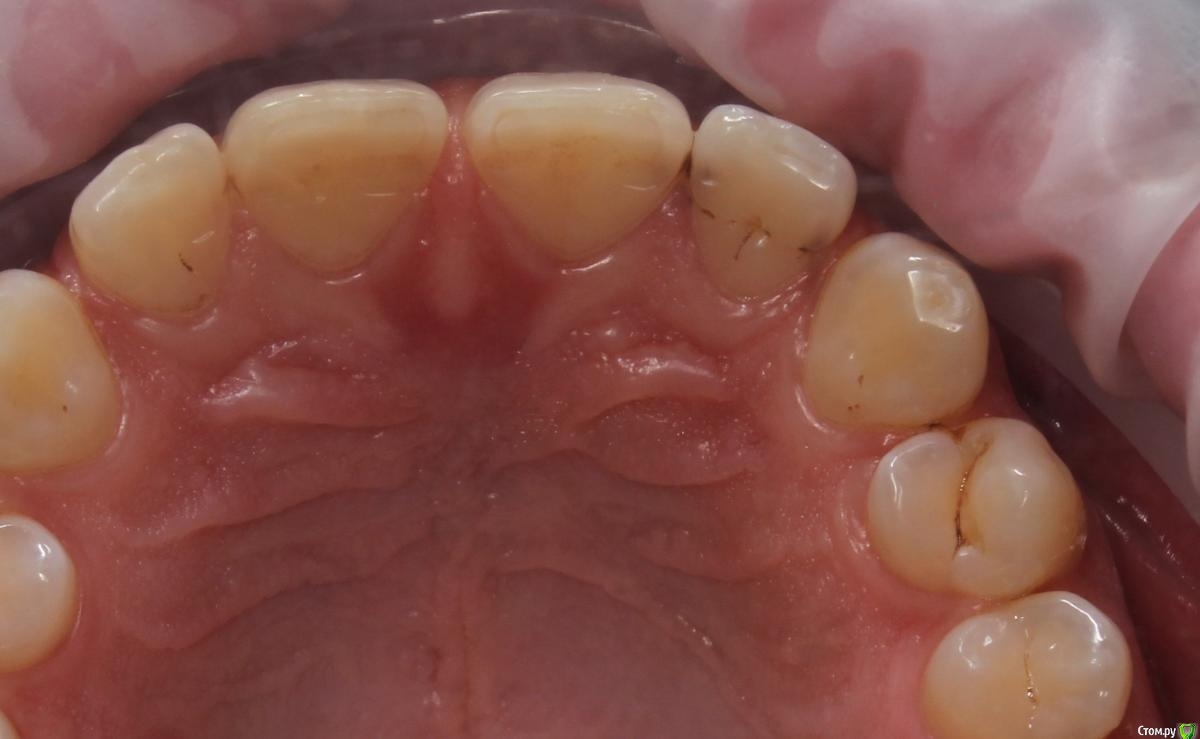

Иго Опубликовано 22 октября, 2020 Поделиться Опубликовано 22 октября, 2020 Здравствуйте!На двойке пятна по краям. Кто-то говорит лечить, а кто- то наблюдать. Что делать? Благодарю за помощь заранее. Ссылка на комментарий

shishok Опубликовано 22 октября, 2020 Поделиться Опубликовано 22 октября, 2020 И на центральном резце тоже. 1 Ссылка на комментарий

DmitrySH Опубликовано 22 октября, 2020 Поделиться Опубликовано 22 октября, 2020 Там уже нормальный кариес, а не пятна. лечить 1 Ссылка на комментарий